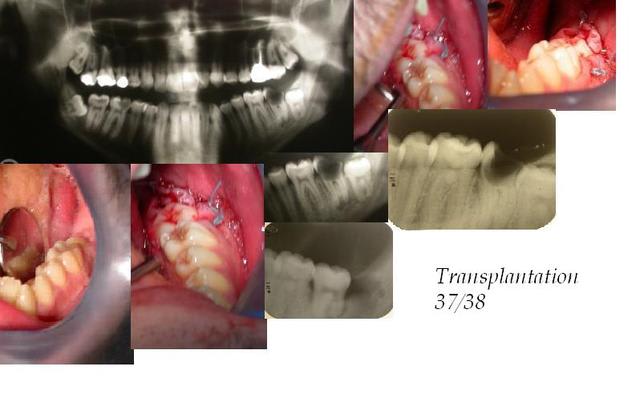

Petit exercice de style.

A 6 mains.

37/38

Patient 21ans, fumeur.

Ce n'est qu'un exercice de style.

Nous avons décidé de réaliser cette transplantation dans un but avant tout pédagogique. Elle présentait environ toutes les contres indications : patient peu (pour ne pas dire "pas") motivé, contrôle de plaque presque inexistant (il n'y a qu'à voir l'état de la 37), la 38 avait largement finie son édification apicale. De plus il fallait voir la tête du patient quand je lui ai dit de ne pas fumer de la journée (même du tabac)!!

L'extraction de la 38 fut relativement difficile, ce qui explique qu'elle ai pris quelques coups de "Zekria-Chir".

Le site implantaire fut aménagé à la fraise boulle sur pièce à main après évaluation de l'espace nécessaire (tout simplement en essayant de la mettre dedans). Puis elle a patienté dans du sérum physiologique (5 à 10 minutes) le temps que la place soit faite.